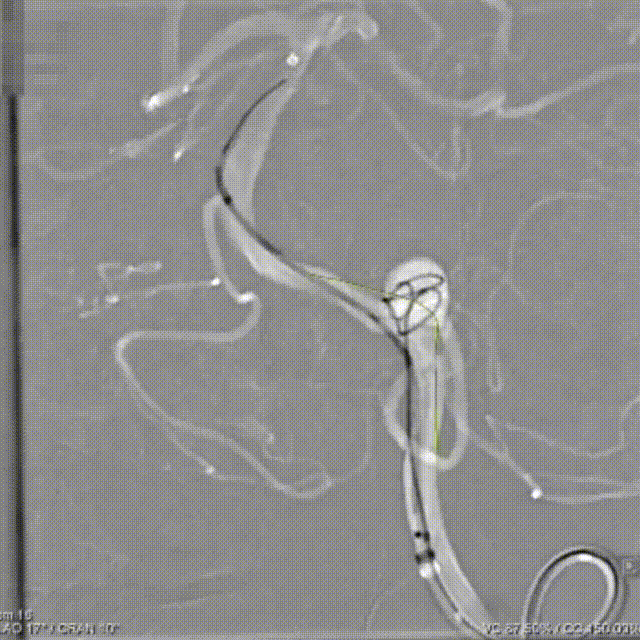

Tubridge Plus Case 2